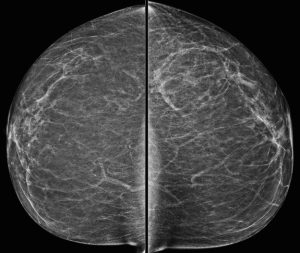

A 71-year-old woman presents with a palpable lump. A BB skin marker is placed over the area of concern and a diagnostic mammogram is performed.

Explanation: The metallic BB marker overlies the axilla and is only seen on the MLO projection. On that image, we see a definitely enlarged lymph node and a second lymph node inferiorly that is also probably enlarged.